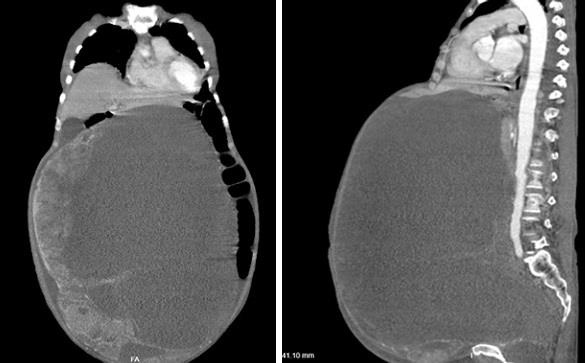

| Khối u chiếm gần hoàn toàn ổ bụng, đè ép các cơ quan. Ảnh: BVCC |

Các bác sĩ khoa Ung bướu đã tiến hành hội chẩn cùng các khoa liên quan và tiến hành phẫu thuật cắt trọn khối u vào ngày 19/3. Cuộc mổ khá khó khăn do u quá lớn, kích thước 30x50 cm, trọng lượng gần 30 kg và dính nhiều vào ruột, thành bụng.